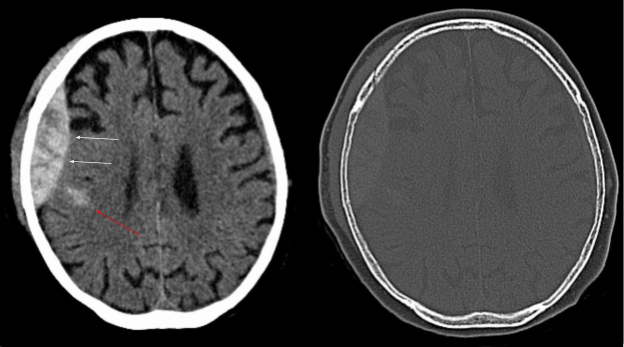

Epidural Hematoma

Epidural hematomas appear convex, or lens-shaped, on CT and do not cross suture lines. An example of a CT scan of an epidural hematoma is shown on Image 3.

Image 3. CT scan of an epidural hematoma (white arrows). Red arrow demonstrates an area of intracerebral hemorrhage. Arrows have been added Image courtesy of: https://commons.wikimedia.org/wiki/File:Epidurale_Blutung_-_CT_-_WT-KF.jpg, This file is licensed under the Creative Commons Attribution-Share Alike 3.0 Unported license.